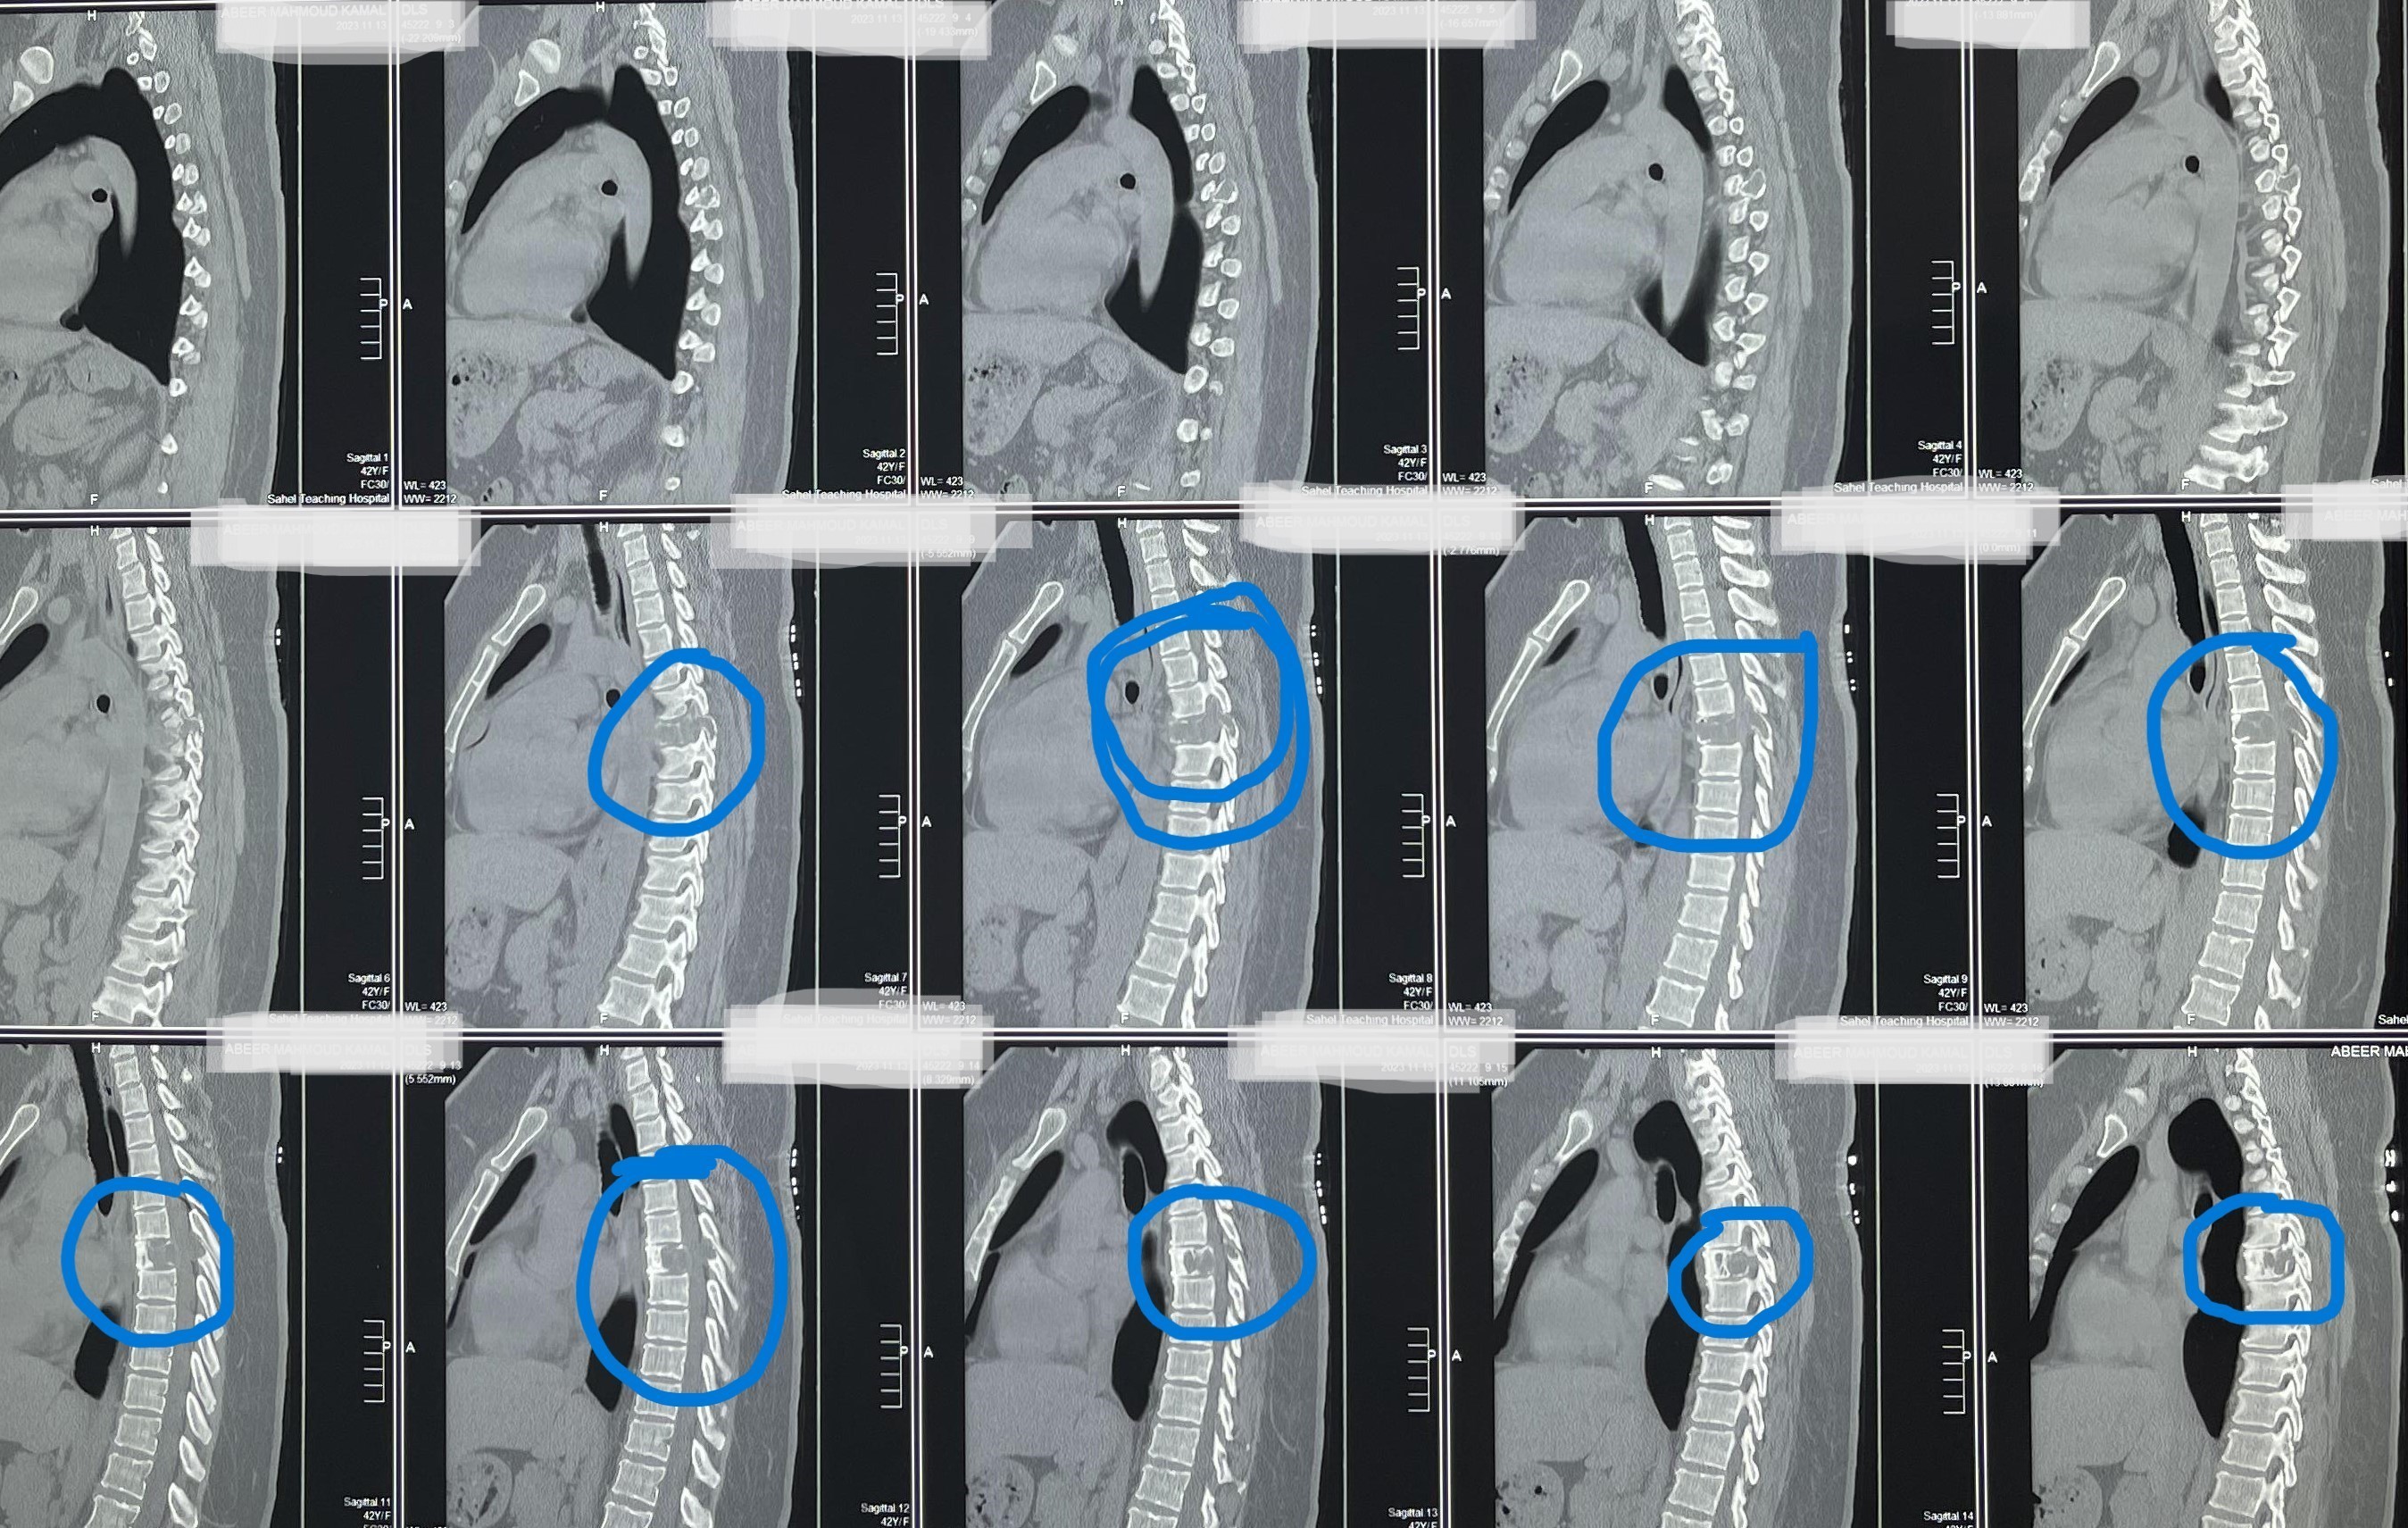

مريضة عمرها 43 عام تعاني من ضعف متزايد بالطرفين السفليين.

43-year-old female patient suffers from increasing weakness in the lower extremities

A 43-year-old woman suffering from progressive weakness in both lower limbs was diagnosed and treated. This condition affects walking ability and mobility, requiring thorough neurological evaluation to determine the underlying cause and develop an appropriate treatment plan.

• Accurate diagnosis using latest neuroimaging techniques